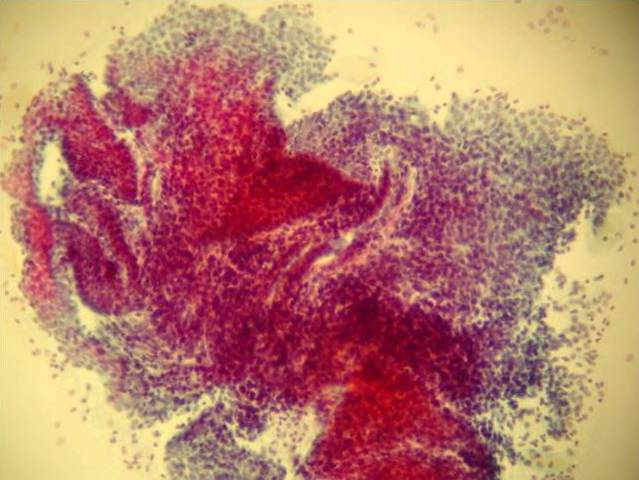

Cytology description

- Reported in peritoneal fluid and fine needle aspiration of scar tissue following gynecologic procedure (e.g., Caesarean section) (J Cytol 2017;34:61)

- Variably sized, 3 dimensional spherules with periphery of polygonal endometrial cells with larger, hyperchromatic nuclei and moderate amount of cytoplasm, often with a center of stromal cells with hyperchromatic nuclei, scant cytoplasm and indistinct cytoplasmic borders (Cancer Cytopathol 2013;121:582)

- May have admixed hemosiderin laden macrophages